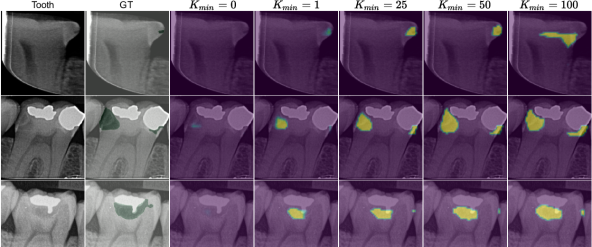

EMIL has two interesting hyperparameters, which we want to explain in more detail: and the patch size. Hyperparameter represents the minimum collective weight that must be assigned to the set of patches to be able to obtain a confident positive classification (i.e., ). For simplicity, consider the case where attention weights can only take on values in . Then can be thought of as the minimum number of patches that must be attended to. If this constraint is violated, the denominator of Eq. 4 turns into a constant, and the network is incentivized (for the positive class) to attend to more patches by increasing through the nominator. Note that the value of also depends on , i.e., attended patches must be classified positively to obtain a high positive class score. Fig. LABEL:fig:tooth_scores shows the effect of on the patch weight map. For increasing values of , sensitivity increases but precision decreases. If the value is too high, performance decreases because healthy tooth regions will be attended, which erroneously reduces disease probability (see, e.g., the first row of Fig. LABEL:fig:tooth_scores). When , little attention is assigned to any patch because all possible class scores can be obtained independent of . According to the standard MIL assumption Dietterich et al. (1997); Foulds and Frank (2010), a single positive instance is sufficient to positively label a bag, therefore is set to 1 and must not be searched.

fig:tooth_scores